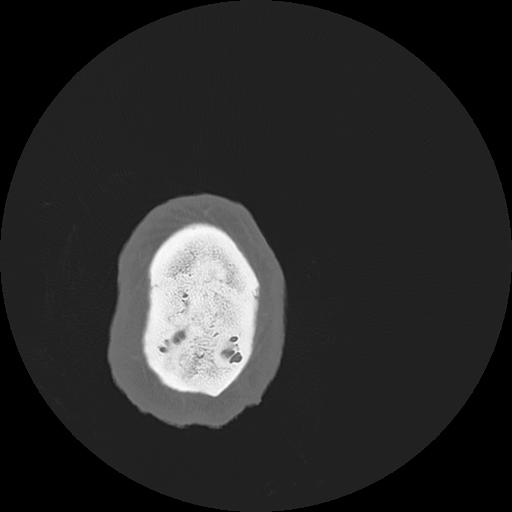

7 HUESO,,Vol,0.5,HUESO,,